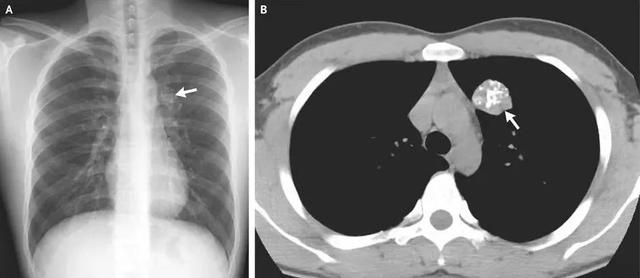

在甲状腺疾病中,恶性病变(如甲状腺癌)和良性病变(如结节性甲状腺肿)均可能存在钙化灶。甲状腺钙化大致可分为微钙化、粗大钙化和边缘环形钙化。

微钙化通常小于2毫米,表现为点状、针尖样、沙粒状钙化,在甲状腺乳头状癌患者中常见,但也并非有了这种钙化就是癌。

粗大钙化表现为片状、弧形或其他不规则形钙化,通常发生在良性结节性甲状腺肿患者中。

边缘环形钙化,一般出现在良性结节中。